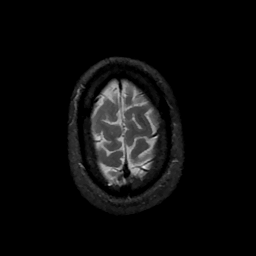

MR Study #11, May 5, 1991 -- Slice #45

[Home][Help][Clinical][Tour 1][Tour 2] Slice 45